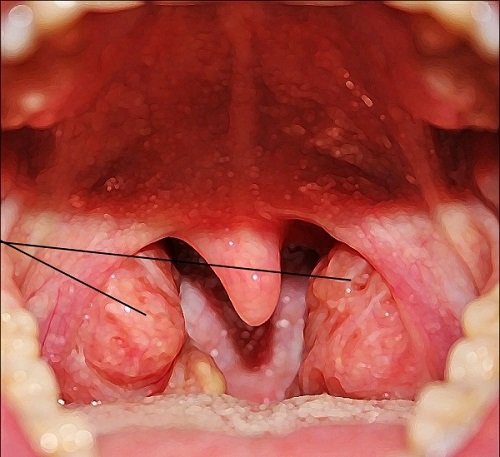

В силу определённых причин (например, частых простудных заболеваний) защитные функции миндалин снижаются, а сами они увеличиваются. Когда разрастается единственная глоточная миндалина (она расположена дальше всех остальных, за свисающим с нёба язычком), врач ставит диагноз «аденоиды». Защитные функции такой гипертрофированной миндалины уже значительно снижены, более того, на ней могут поселиться патогенные микроорганизмы, превращая иммунный орган в источник хронической инфекции (отсюда и характерный неприятный запах изо рта, который часто имеет место при аденоидах).

В силу определённых факторов глоточная миндалина начинает разрастаться, утрачивая свою защитную функцию

Многие люди, не слишком разбирающиеся в медицинских терминах, путают понятия «аденоиды» и «гланды». На самом деле гланды — это парные миндалины, расположенные на нёбе, их воспаление называется тонзиллит. Аденоиды же имеют отношение уже к другой миндалине — глоточной (непарной). Чтобы обнаружить её разрастание, врачу требуется специальное зеркало, в то время как воспаление гландов заметно при обычном осмотре горла.

Естественно, помимо данных признаков, разрастание аденоидов фиксируется при осмотре глотки (используется специальное зеркало). Операция назначается обычно при аденоидах 3-й степени (при данной стадии лекарственная терапия, как правило, уже неэффективна).